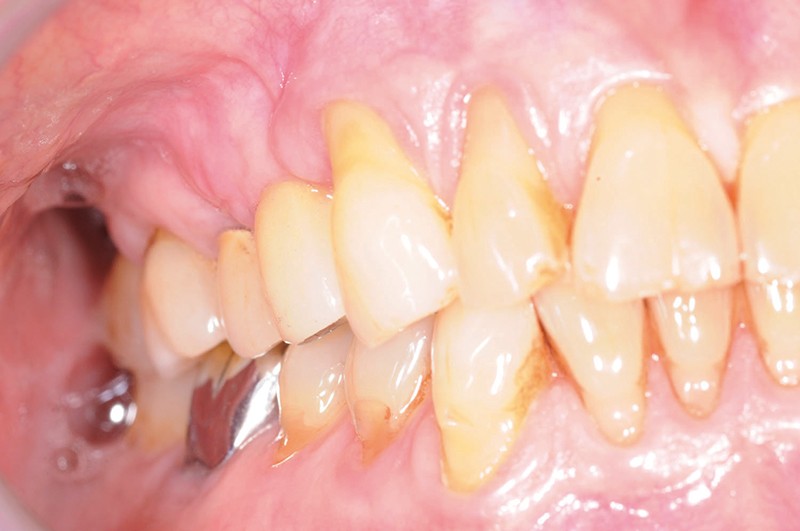

Lors de la maintenance de 2016, le contrôle de plaque de la patiente est toujours excellent et les tissus implantaires ne présentent pas de signes inflammatoires(fig. 2a et b).